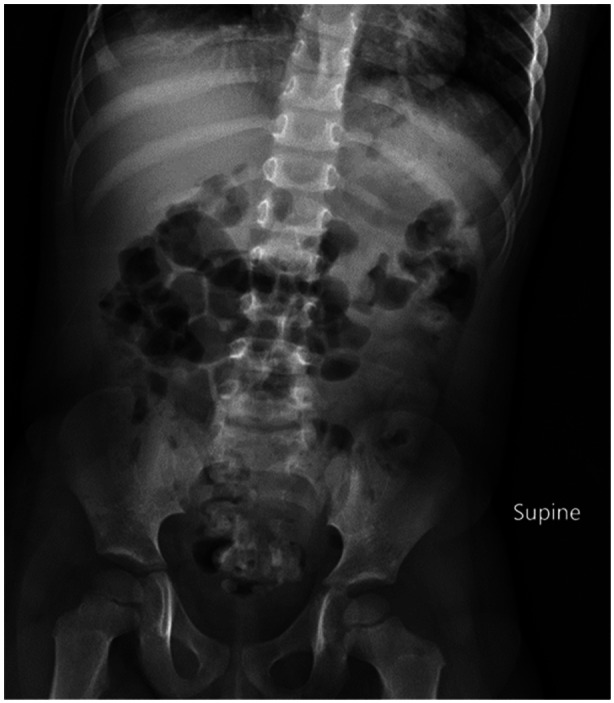

Kinetic magnetic sand, composed of ultra-fine sand and dimethicone in a 98%-2% ratio, is a versatile sensory toy known for its moldable properties and structural stability (1). Despite the name, it lacks actual magnetic features. Ingesting kinetic sand can pose risks, including choking and gastrointestinal issues, especially in young children. This case report details a unique incident involving a 3-year-old who ingested a significant amount of kinetic sand. Although the sand's ingredients are generally hypoallergenic and nontoxic, its grainy texture presented challenges for retrieval. The patient was closely monitored, and ultimately, the sand passed without complications. While no official guidelines exist for managing such cases, individual assessments, considering factors such as ingestion time, symptoms, and age, are crucial for determining the appropriate course of action, which may range from observation to more invasive procedures like endoscopy or surgery.